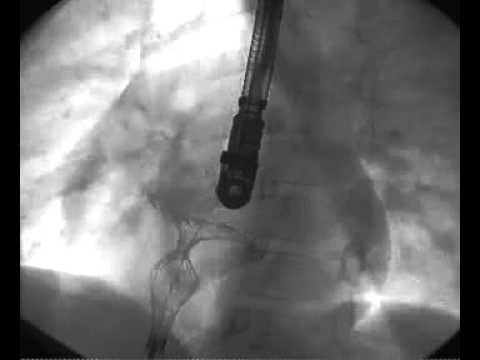

Transcatheter Closure - Movie 4: Left atrial disc configuration

Transcatheter Closure - Movie 5: Waist and right atrial disc configuration